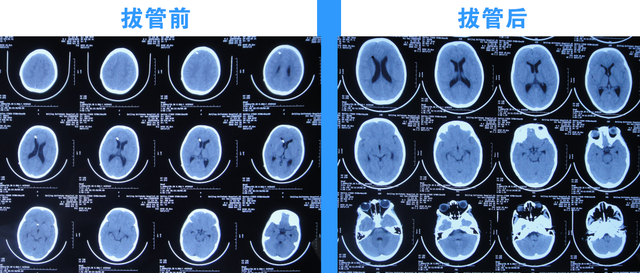

2022年10月19日(住院治疗111天),拔除了脑室引流术,拔管前和拔管后头颅CT(图-18)对比。

图-18:2022年10月19日拔管前后头颅CT对比